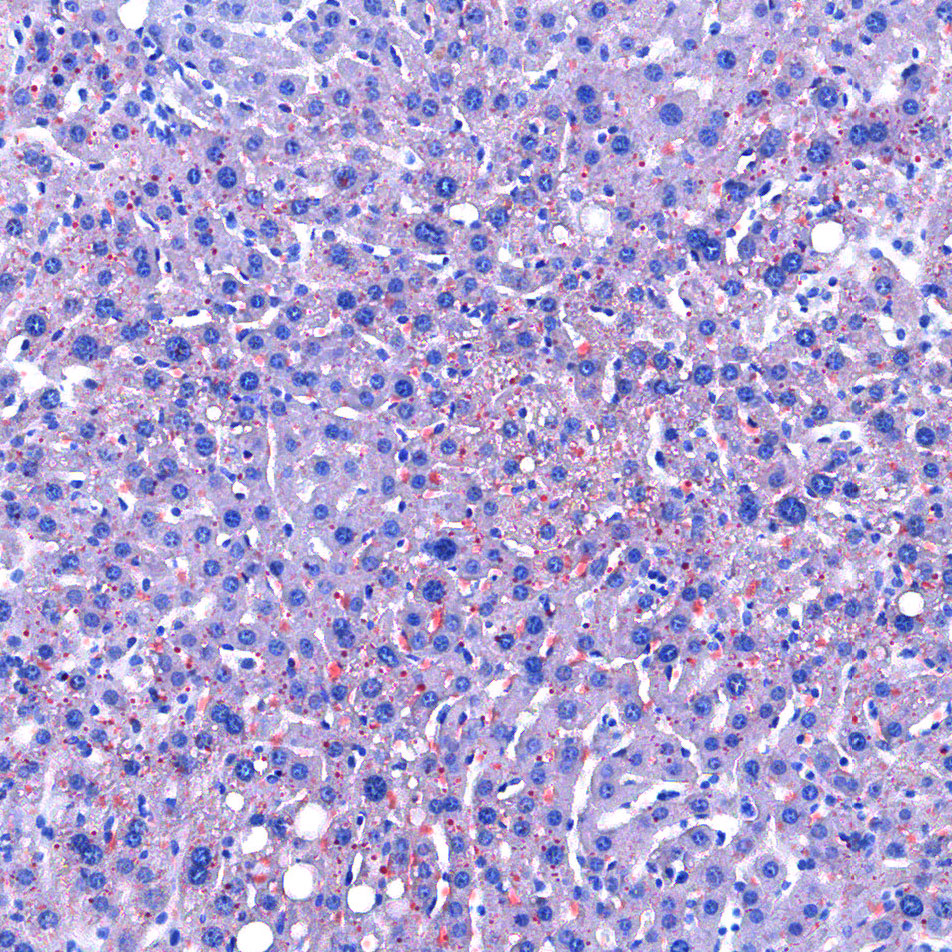

技术原理

油红O对脂滴的染色机制一般认为是物理学上的溶液作用或吸附作用,借溶液作用使脂质染色,即油红O先溶于60%异丙醇中,然后切片浸入油红O染液中时,油红O在组织脂质的溶解度较60%异丙醇中的溶解度高,所以在染色时油红O从60%异丙醇中转移入脂质中使脂滴显示红色。

实验结果展示:

<油红O-肝>